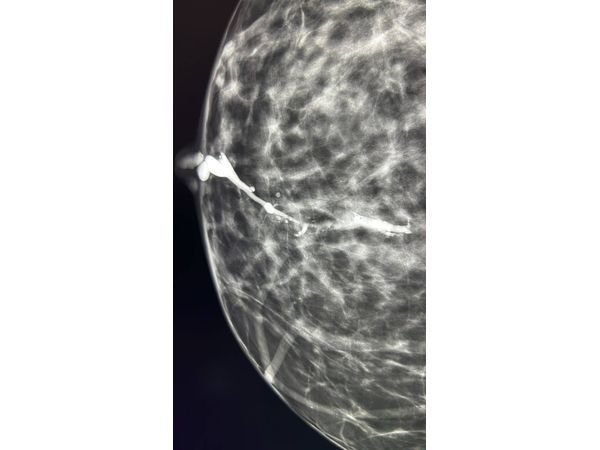

При цифровой маммографии узловых образований и подозрительных кальцитов не было обнаружено, определялась умеренно выраженная фиброгландулярная ткань молочных желёз (т. е. нормальная соединительная и железистая ткань). По результату исследования, для обеих молочных желёз выставлена категория BI-RADS 2 — типично доброкачественные изменения.

Пациентке сделали дуктографию — рентгеноконтрастное исследование протоков молочной железы. В проток, из которого появлялись выделения, ввели 0,5 мл контрастного вещества Омнипак и выполнили маммографические снимки в двух проекциях: прямой и боковой. На снимках в 3 см от соска, в проекции нижне-внутреннего квадранта правой молочной железы определялся дефект наполнения размером до 1,5 см. Было сделано заключение: внутрипротоковое разрастание правой молочной железы — BI-RADS 4а (подозрение на злокачественное образование, но с низкой вероятностью рака).